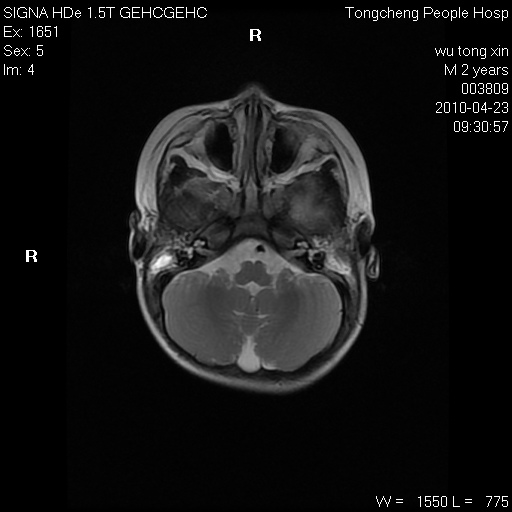

以下是引用赵物学在2010-4-25 12:43:00的发言:[br]巨脑回[br]侧脑室后角低密度影考虑hie或肾上腺脑白质营养不良?[br][br][本贴已被 赵物学 于 2010-4-25 12:51:28 修改过]

以下是引用gaoxiao在2010-4-25 16:54:00的发言:[br]巨脑回畸形。脑白质髓鞘化不良

以下是引用pujunzhi在2010-4-25 21:35:00的发言:[br]考虑 1双侧大脑皮质发育不良 2轻度脑积水 3双侧脑室后角旁片状长t1长t2信号,需继续观察,因为正常小儿此处脑白质的髓鞘化时间可以延迟到4-6岁,才显示正常。